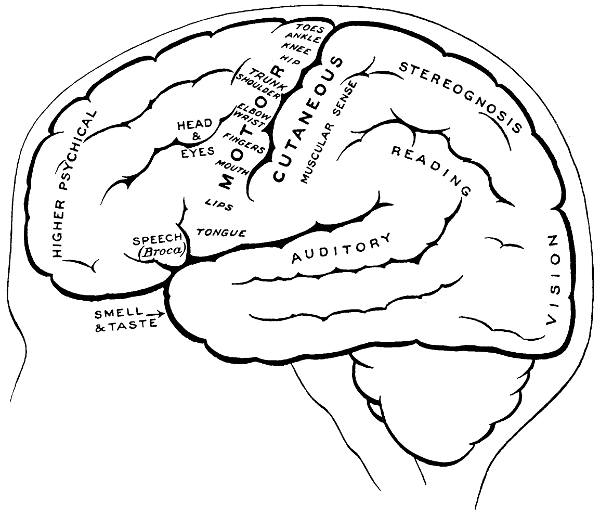

| 3. The cortical motor and sensory areas | 8 |

| 58. The cortical motor and sensory areas | 165 |

| 68. The cortical motor and sensory areas | 220 |

The researches of Sherrington and Grünbaum,[2] Campbell,[3] and others tend to show that the cortical motor areas are situated entirely anterior to the central fissure or fissure of Rolando, extending above well over on to the mesial aspect of the brain, though not so far as the calloso-marginal fissure, and in the downward direction to within a short distance of the fissure of Sylvius. In the posterior direction the motor area includes the anterior boundary and part of the bottom of the fissure of Rolando, whilst in front it spreads, by means of gyri annectantes, on to that part of the brain which lies anterior to the precentral sulcus. The anterior termination is indefinite, but the motor strip is, on an average, not more than 3⁄4 inch in breadth.

The genua of the Rolandic fissure are said to bear a more or less definite relation to the motor areas. In my experience, however, they are too variable, and any importance which might obtain is further diminished by the fact that the surgeon should never rest content with that limited exposure of the brain which was so much in vogue till recent years. The suspected region is widely exposed by osteoplastic flap, and if doubt exists as to the particular part of cortex exposed the question is accurately settled by faradization.

This motor strip corresponds, from above downwards, to the movements of the contralateral lower extremity (toe to hip), trunk, upper extremity (shoulder to fingers), neck and face. It is a point of some general utility to bear in mind that the temporal crest intervenes approximately between the regions responsible for the movements of the upper extremity (above the crest) and those for the movements of the head and face (below the crest).

Fig. 3. The Cortical Motor and Sensory Areas.

On the left side of the head—in normal right-handed individuals—the motor speech area of Broca corresponds to the third left frontal convolution, in the angle between the anterior and posterior horizontal limbs of the Sylvian fissure.

The ‘primary registration’ of ‘common sensation’ occurs in the post-central gyrus, immediately posterior to the fissure of Rolando. This tactile area occupies a position behind the fissure of Rolando[9] similar in extent to that occupied by the motor area in front. It commences at the bottom of the fissure of Rolando and extends backwards over rather more than half the exposed area of the post-central convolution. It reaches down to near the Sylvian fissure and extends over on to the mesial aspect of the brain. Furthermore, it is probable that sensation in any given part lies on more or less the same level as the corresponding motor area.

Immediately posterior to the tactile area and occupying the posterior and upper part of the post-central convolution, the area responsible for muscle-sense is situated.

Stereognosis—memory pictures, object perception, &c.—is referred to the superior parietal lobe.

Primary visual impressions are received in the occipital lobe, more especially on the mesial aspect thereof.

Finally, the four areas concerned in speech—motor speech, writing, reading, and hearing—are anatomically separated from one another and yet closely associated, so much so that one can hardly be involved without the other. The motor speech centre of Broca has already been mentioned as occupying—in right-handed individuals—the posterior part of the third left frontal convolution. Writing lies immediately above and in front, in the posterior part of the middle frontal gyrus, auditory impressions are received in the posterior and upper part of the first temporo-sphenoidal lobe, whilst the power of reading is dependent on the integrity of the supramarginal and angular gyri (see also Fig. 57).

Smell and Taste lie in close relation to the anterior pole of the temporo-sphenoidal lobes.